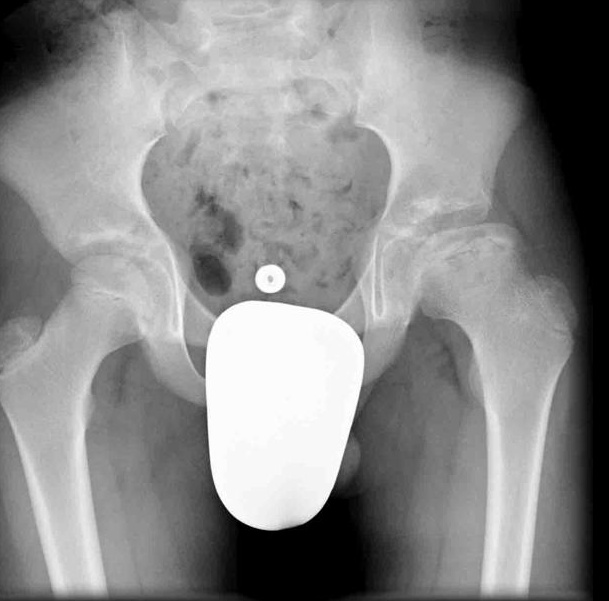

X-ray imaging is the preferred method of viewing developmental dysplasia of the hip after the femoral head begins ossifiying at 4-6 months of age.

Treatment of developmental dysplasia of the hip in children 6 months old to 2 years of age involves either closed or open reduction followed by Spica casting.